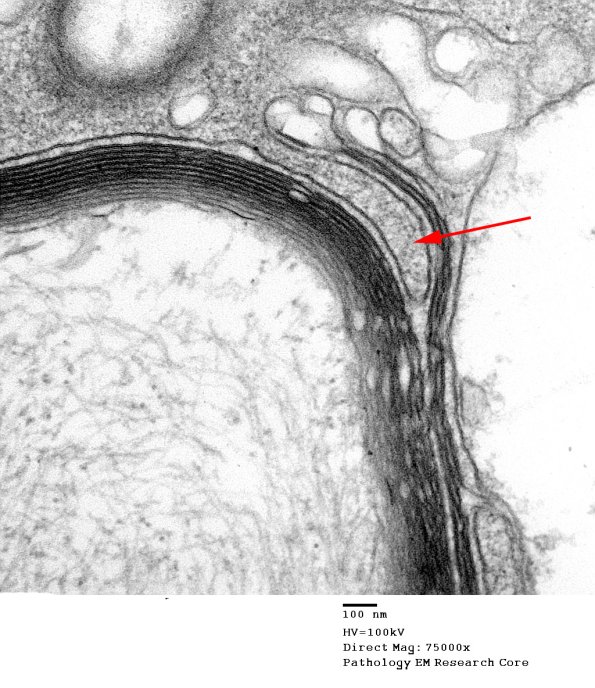

These micrographs show increasing magnification of a part of the myelin sheath undergoing stripping. A macrophage process separates Schwann cell cytoplasm from its underlying intact myelin and insinuates cytoplasmic fingers into the intraperiod lines of the myelin sheath (arrow). (electron micrographs